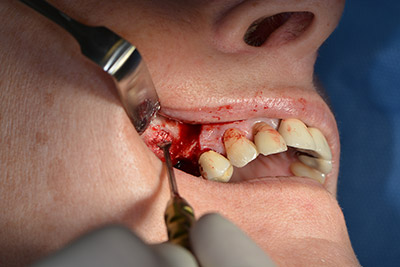

The following holes were drilled at a reduced speed of 300 rpm. The Implantmed demonstrated its true capability at this stage. The surgical protocol can be preset – the various positions can be selected simply by pressing the “P” position of the foot control (Fig. 10 to 11).

The next programmed position is the placement of the implant and in our practice it is preset to a force of 32 Ncm (Fig. 12).

The next step was the sinus floor elevation with simultaneous implantation. The Implantmed also had a presetting at the first position for the buccal fenestration of the maxillary sinus wall.

The fenestration was prepared at 35,000 rpm and then the nasal mucosa were prepared in the cranial direction (Fig. 13 to 14).